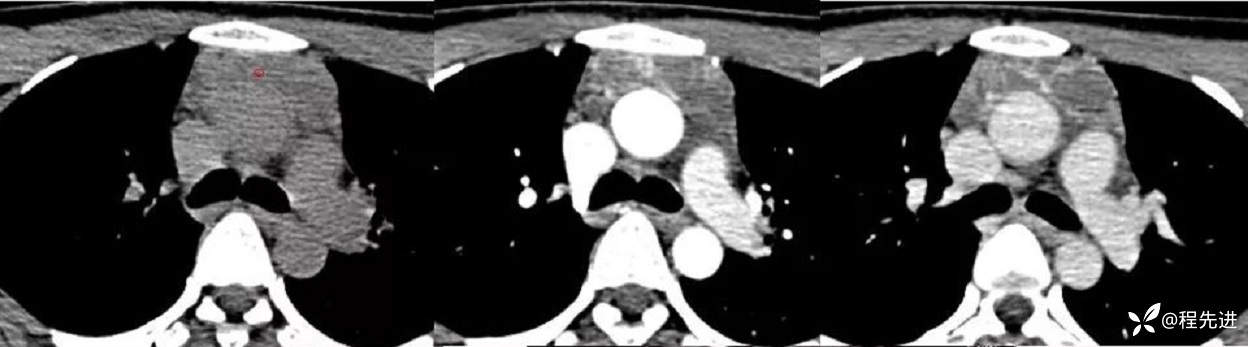

CT平扫+增强

平扫CT值:65HU/动脉期CT值:75HU/静脉期CT值:82U

冠状位、矢状位重建